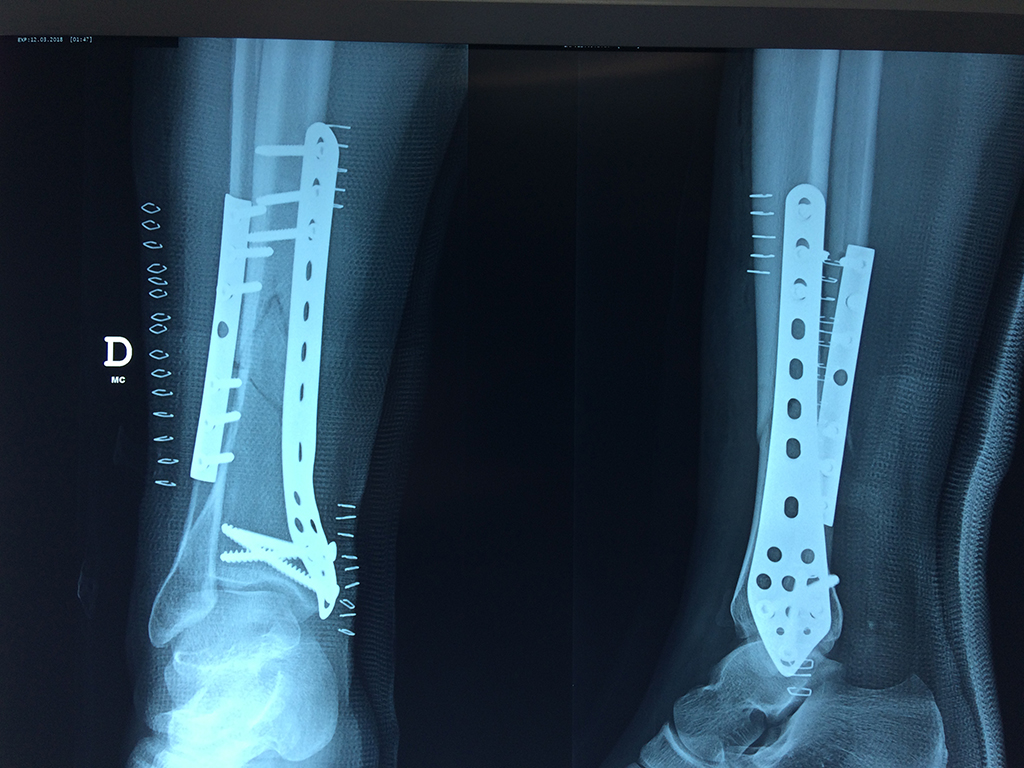

Cirugías de Hombros - Perone y Tibia

Aunque cada uno de estos huesos puede fracturarse por separado, normalmente la rotura es una lesión que se produce de forma conjunta

La mayor parte de las roturas implican a la parte proximal del hueso (parte del hueso próximo a la rodilla) o a la parte distal (parte del hueso cerca del tobillo).

Debido a la fina cobertura de piel que recubre la tibia y el peroné, las fracturas generalmente son abiertas, es decir, el hueso roto rasga la piel, atravesándola. Las fracturas de tibia y peroné generalmente se producen por un fuerte impacto o torsión.